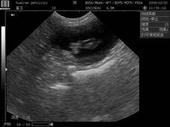

患者病情描述:我上个月与老公同房,事后发现避孕套破了,又吃了事后紧急避孕药,但是昨天我用试纸测试怀孕了,我现在想做B超确认一下,请问医生,怀孕多久做b超可以检查出来?这个孩[详情]